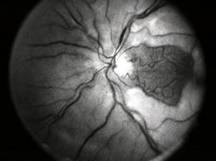

Retinal Detachment |

Retinal Detachment (R.D.) is a separation of the sensory retina from the retinal pigment epithelium(R.P.E) by sub retinal fluid(S.R.F) There are two main types.

Secondary R.D sub divided in to two types:

Retinal signs depends on duration of R.D.